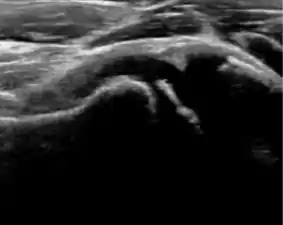

Ultrasound allows categorizing pediatric hips, according to Graf’s criteria, in four main types: normal, immature, and dysplastic (subluxed and dislocated). This classification is based on measurements of the acetabular inclination angle (alpha), cartilage roof angle (beta), and infant age. The femoral head coverage can also be determined by dividing the length of the femoral head covered by the acetabular fossa and the diameter of the femoral head. Its lower normal limits are 47% for boys and 44% for girls (Figure 11).[1]

Figure 11:

Useful ultrasound measures in neonatal hip sonography, alpha and beta angles.[1]

Measurement of femoral head coverage.[1]

In a recent study, including newborns with high clinical suspicion for DDH (Ortolani/Barlow test, asymmetry in abduction of 20° or greater, breech presentation, leg-length discrepancy, and first-degree relative treated for DDH), hip sonography led to a change in clinical diagnosis in 52% of hips and to a change in management plan in 32% of hips. It obviated further follow-up in 23%, strengthening its role as an important technique reassuring the clinical diagnosis.[1]

During childhood, ultrasound is a quick method to assess hip pain and quite often may be used to avoid use of irradiating techniques, such as radiography or CT. Ultrasound allows evaluation of joint effusion, synovial thickening and neovascularity, the bone/cartilage contour, and the femoral head-neck alignment. Although sonography is extremely sensitive in detecting increased synovial fluid, it is nonspecific and cannot be used with accuracy to determine the type of fluid. Transient synovitis of the hip, despite being the most frequent cause of pain in children between 3 and 10 years, remains a diagnosis of exclusion. It usually shows anechoic fluid, but echogenic fluid can also be found. The effusion is considered pathologic when it is measured at >2 mm in thickness. The differential diagnosis is wide, including osteomyelitis, septic arthritis, primary or metastatic lesions, LCPD, and SCFE. Discrimination from septic arthritis is challenging, often requiring joint aspiration. In septic arthritis, US is able to demonstrate a hip joint effusion, synovial thickening, and cartilage damage, although the appearances are nonspecific.[1]